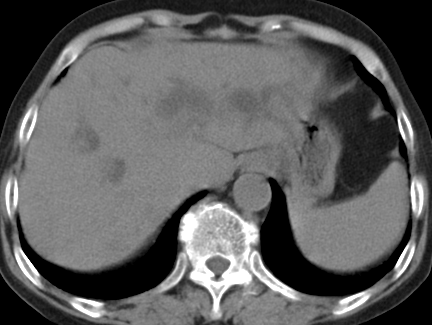

以下是引用齐原在2006-11-8 23:21:00的发言:[br]肝脏体积增大.肝表凸凹不平,肝内胆管扩张,胆总管扩张,胆总管末端突然截断,胰腺勾突增大,形态不规则.胰管扩张.考虑胰头癌.并低位梗阻性胆系扩张,胆囊炎.脾大.建议增强

以下是引用dyqct在2006-11-9 9:14:00的发言:[br]肝大,表面呈波浪状,肝内外胆管扩张,胆总管下端腔内见小结节状等密度影,胰管轻度扩张。胆囊显示不清。[br]考虑:1、胆总管下端占位性病变(等密度结石?壶腹部肿瘤?);[br] 2、肝硬化?[br] 3、建议增强扫描进一步检查。